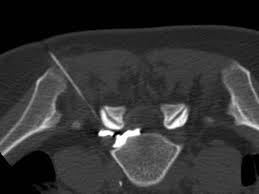

Le geste sera effectué par scanner. Cette technique permet de choisir le bon point d’entrée de l’aiguille et de suivre son trajet.

Pendant l’infiltration, suivez bien les recommandations du médecin et du technicien. Votre coopération est essentielle : elle contribuera à la rapidité du geste de ponction et diminuera les risques de douleur et de complications. Vous êtes installé sur le dos sur une table de scanner. Désinfection très soigneuse de la peau. Sous contrôle scanner une aiguille est mise en place à proximité du nerf. Une faible quantité de produit de contraste iodé est injectée pour vérifier la bonne position de l’extrémité de l’aiguille, puis le médicament est injecté.